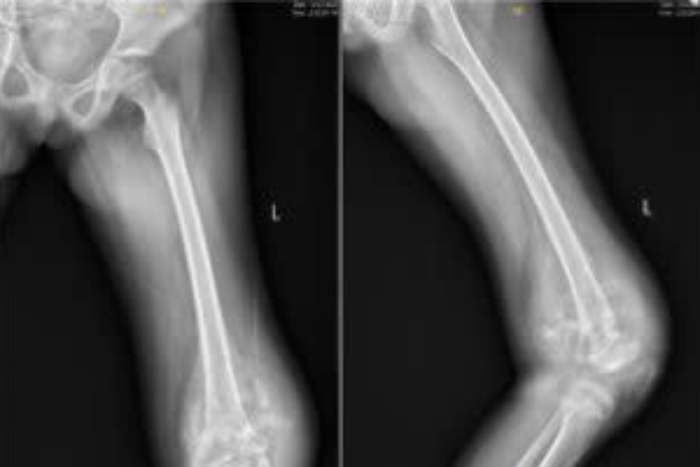

Bé trai được phát hiện ung thư nguy hiểm từ một dấu hiệu ở chânBé trai 10 tuổi sưng đau gối kéo dài, khi đi khám phát hiện bệnh ung thư. Gia cảnh của cậu bé khó khăn nên bác sĩ đã kết nối gia đình với các nhà hảo tâm, giúp chi trả toàn bộ chi phí phẫu thuật giữ lại đôi chân cho trẻ.